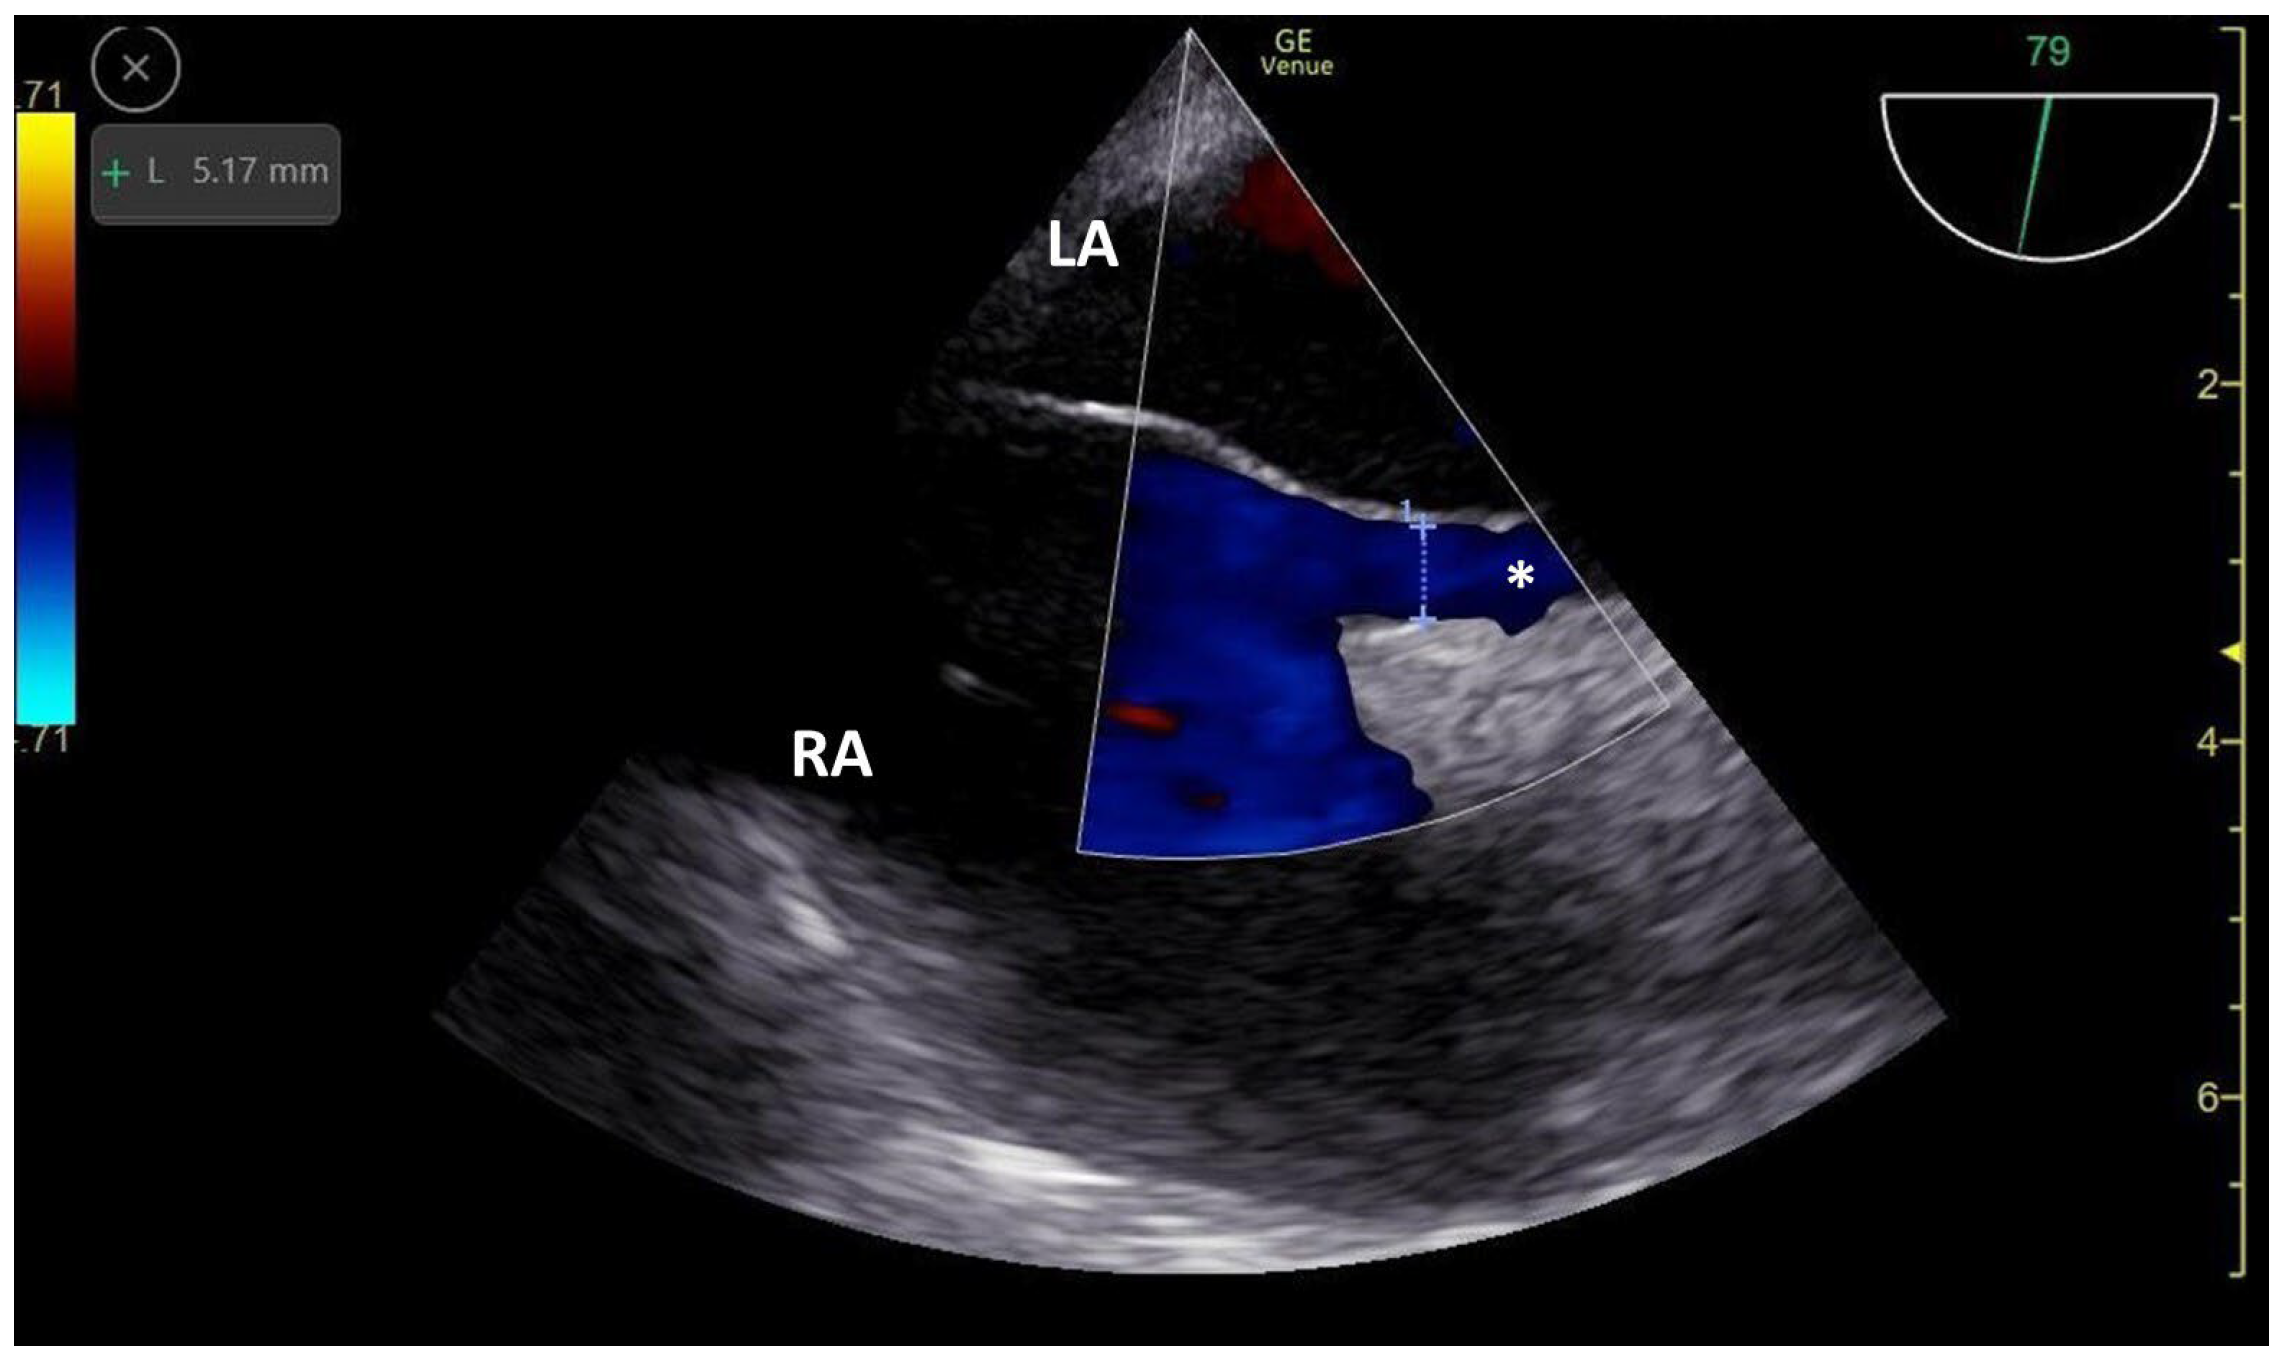

3.2. TCCD MES-Positive Case 2

| PFO | patent foramen ovale |

| TEE | transesophageal echocardiography |